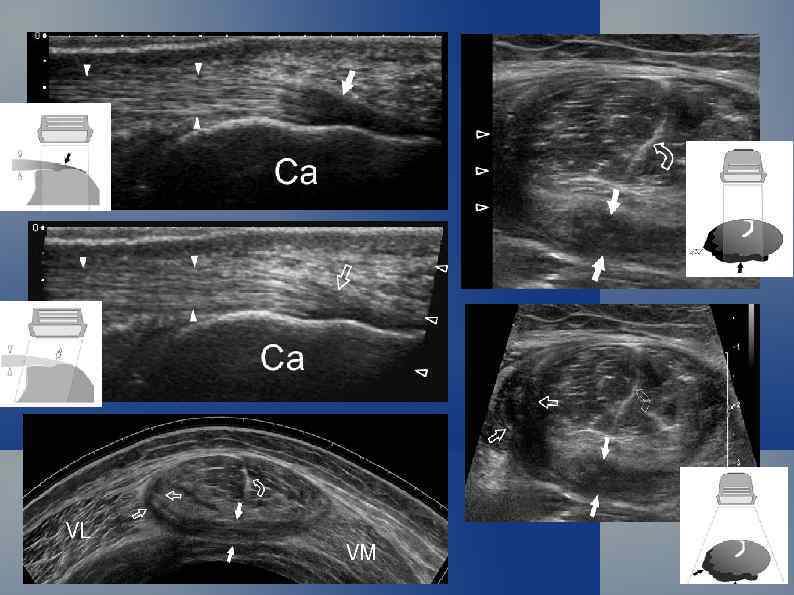

Надколенник Киста жирового тела Гофа В исследовании мышечноскелетной системы действуют те же физические принципы. Акустически плотные структуры (камни, кости, металлические предметы) полностью отражают звуковую волну. Ограниченное скопление жидкости формирует дистальное усиление эхосигнала.

Реверберация. Эпифиз локтевой кости. Эффект анизотропии у сухожилий